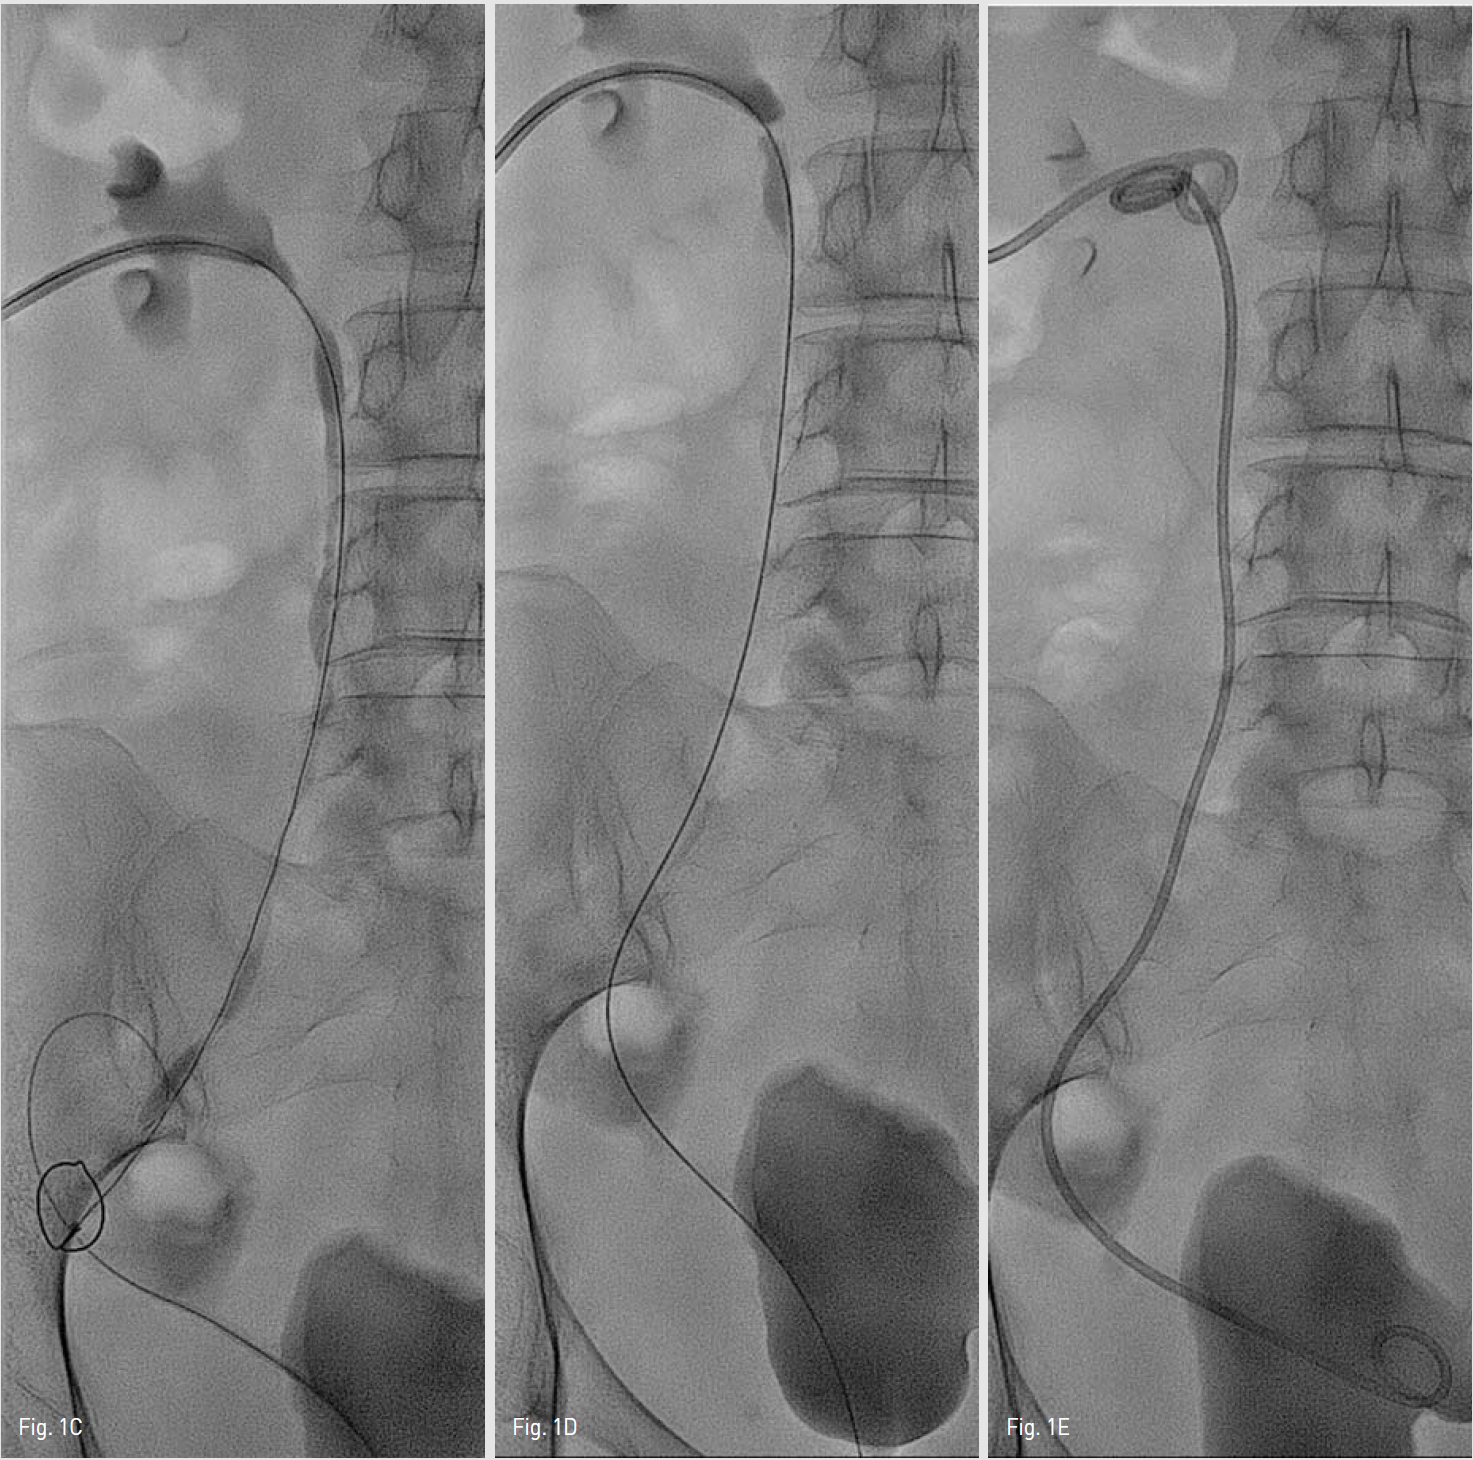

PCN 도관을 통해 시행한 신조엉술에서 좌측 원위부요관에 협착과 함께 다량의 조영제 유출이 관찰되었고(Fig. 1A), 요도를 통해 0.035 인치 유도철사(Terumo, Tokyo, Japan)와 5-Fr Kumpe catheter(Cook, Bloomington, IN, USA)를 삽입하여 방광을 지나 원위부 요관에서 시행한 조영상에서도 조영제 유출이 관찰되었다(Fig. 1B). 요관의 개통성을 유지하기 위해 double J stent 설치하기로 계획하였다. 5-Fr Kumpe catheter와 0.035 인치 유도철사를 이용하여 좌측 원위부 요관의 협착부위를 지나 방광으로 진입을 시도하였으나 유도철사가 요관 파연 부위를 통해 후복막으로

Fig. 1A, B

A-B. Antegrade nephrogram through PCN catheter and retrograde nephrogram through 5-Fr Kumpe catheter show stenosis at distal portion of left ureter with large amount of contrast leakage into the retroperitoneum.